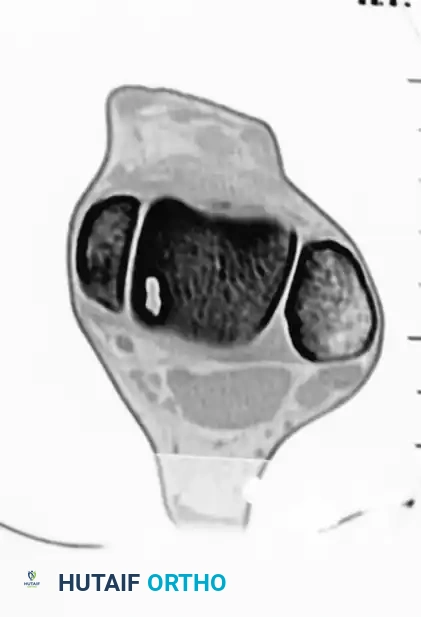

PREOPERATIVE PLANNING AND IMAGING

Thorough preoperative imaging is mandatory to define the lesion's morphology, depth, and precise anatomical location.

- Weight-Bearing Radiographs: Standard anteroposterior (AP), lateral, and mortise views evaluate overall joint space, alignment, and the presence of osteophytes.

- Computed Tomography (CT): CT is the gold standard for evaluating the osseous architecture, identifying subchondral cysts, and determining the exact dimensions of the bony defect.

- Magnetic Resonance Imaging (MRI): MRI is essential for assessing the integrity of the overlying articular cartilage, identifying bone marrow edema, and evaluating concomitant soft tissue injuries (e.g., lateral ligamentous complex tears).